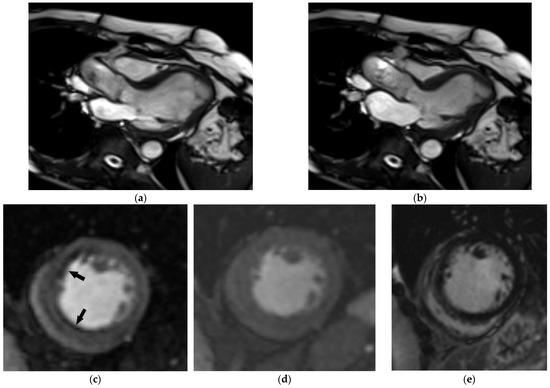

Focal myocardial scarring can be detected using LGE, providing additional prognostic information in HF patients [93]. The distribution of LGE can provide information regarding the etiology of HF, with important therapeutic implications. This is especially the case for ischemic heart disease characterized by subendocardial LGE distribution. An additional value of MRI in ischemic heart disease is the possibility of estimating the viability of myocardium and the hemodynamic significance of coronary artery stenosis via stress imaging, which is of high importance if myocardial revascularization is planned (Figure 7). Additional caution is required during stress MRI in older people, because dipyridamole and regadenoson are more likely to cause hypotension or bradycardia when administered to older versus younger patients, and dobutamine is more likely to induce arrhythmias [37]. Other functional imaging techniques that might be used to detect myocardial ischemia are stress echocardiography, single-photon emission CT (SPECT), and positron emission tomography (PET) [8].

Figure 7.

Comprehensive cardiac MRI in a 74-year-old female patient with a new onset of heart failure. End-diastolic (a) and end-systolic (b) 3-chamber view SSFP image depicting moderately impaired left ventricular systolic function (EF 31%). Midventricular short-axis adenosine-stress (c) and rest (d) perfusion image revealed stress-induced ischemia in the anterolateral and inferolateral wall (arrows) without evident late gadolinium enhancement (e). Coronary angiography chronic occlusion of the mid-LAD, as well as high-grade stenosis of mid-RCA and D1, were confirmed and treated.